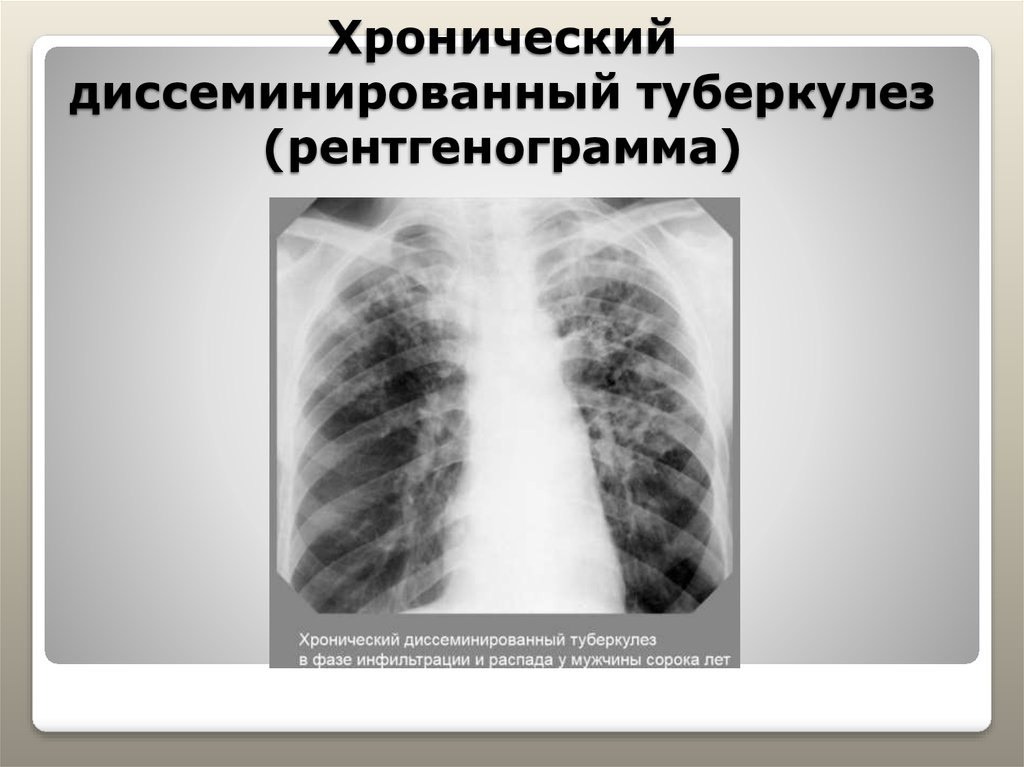

В клинической картине острого гематогенно диссеминированного туберкулеза преобладает